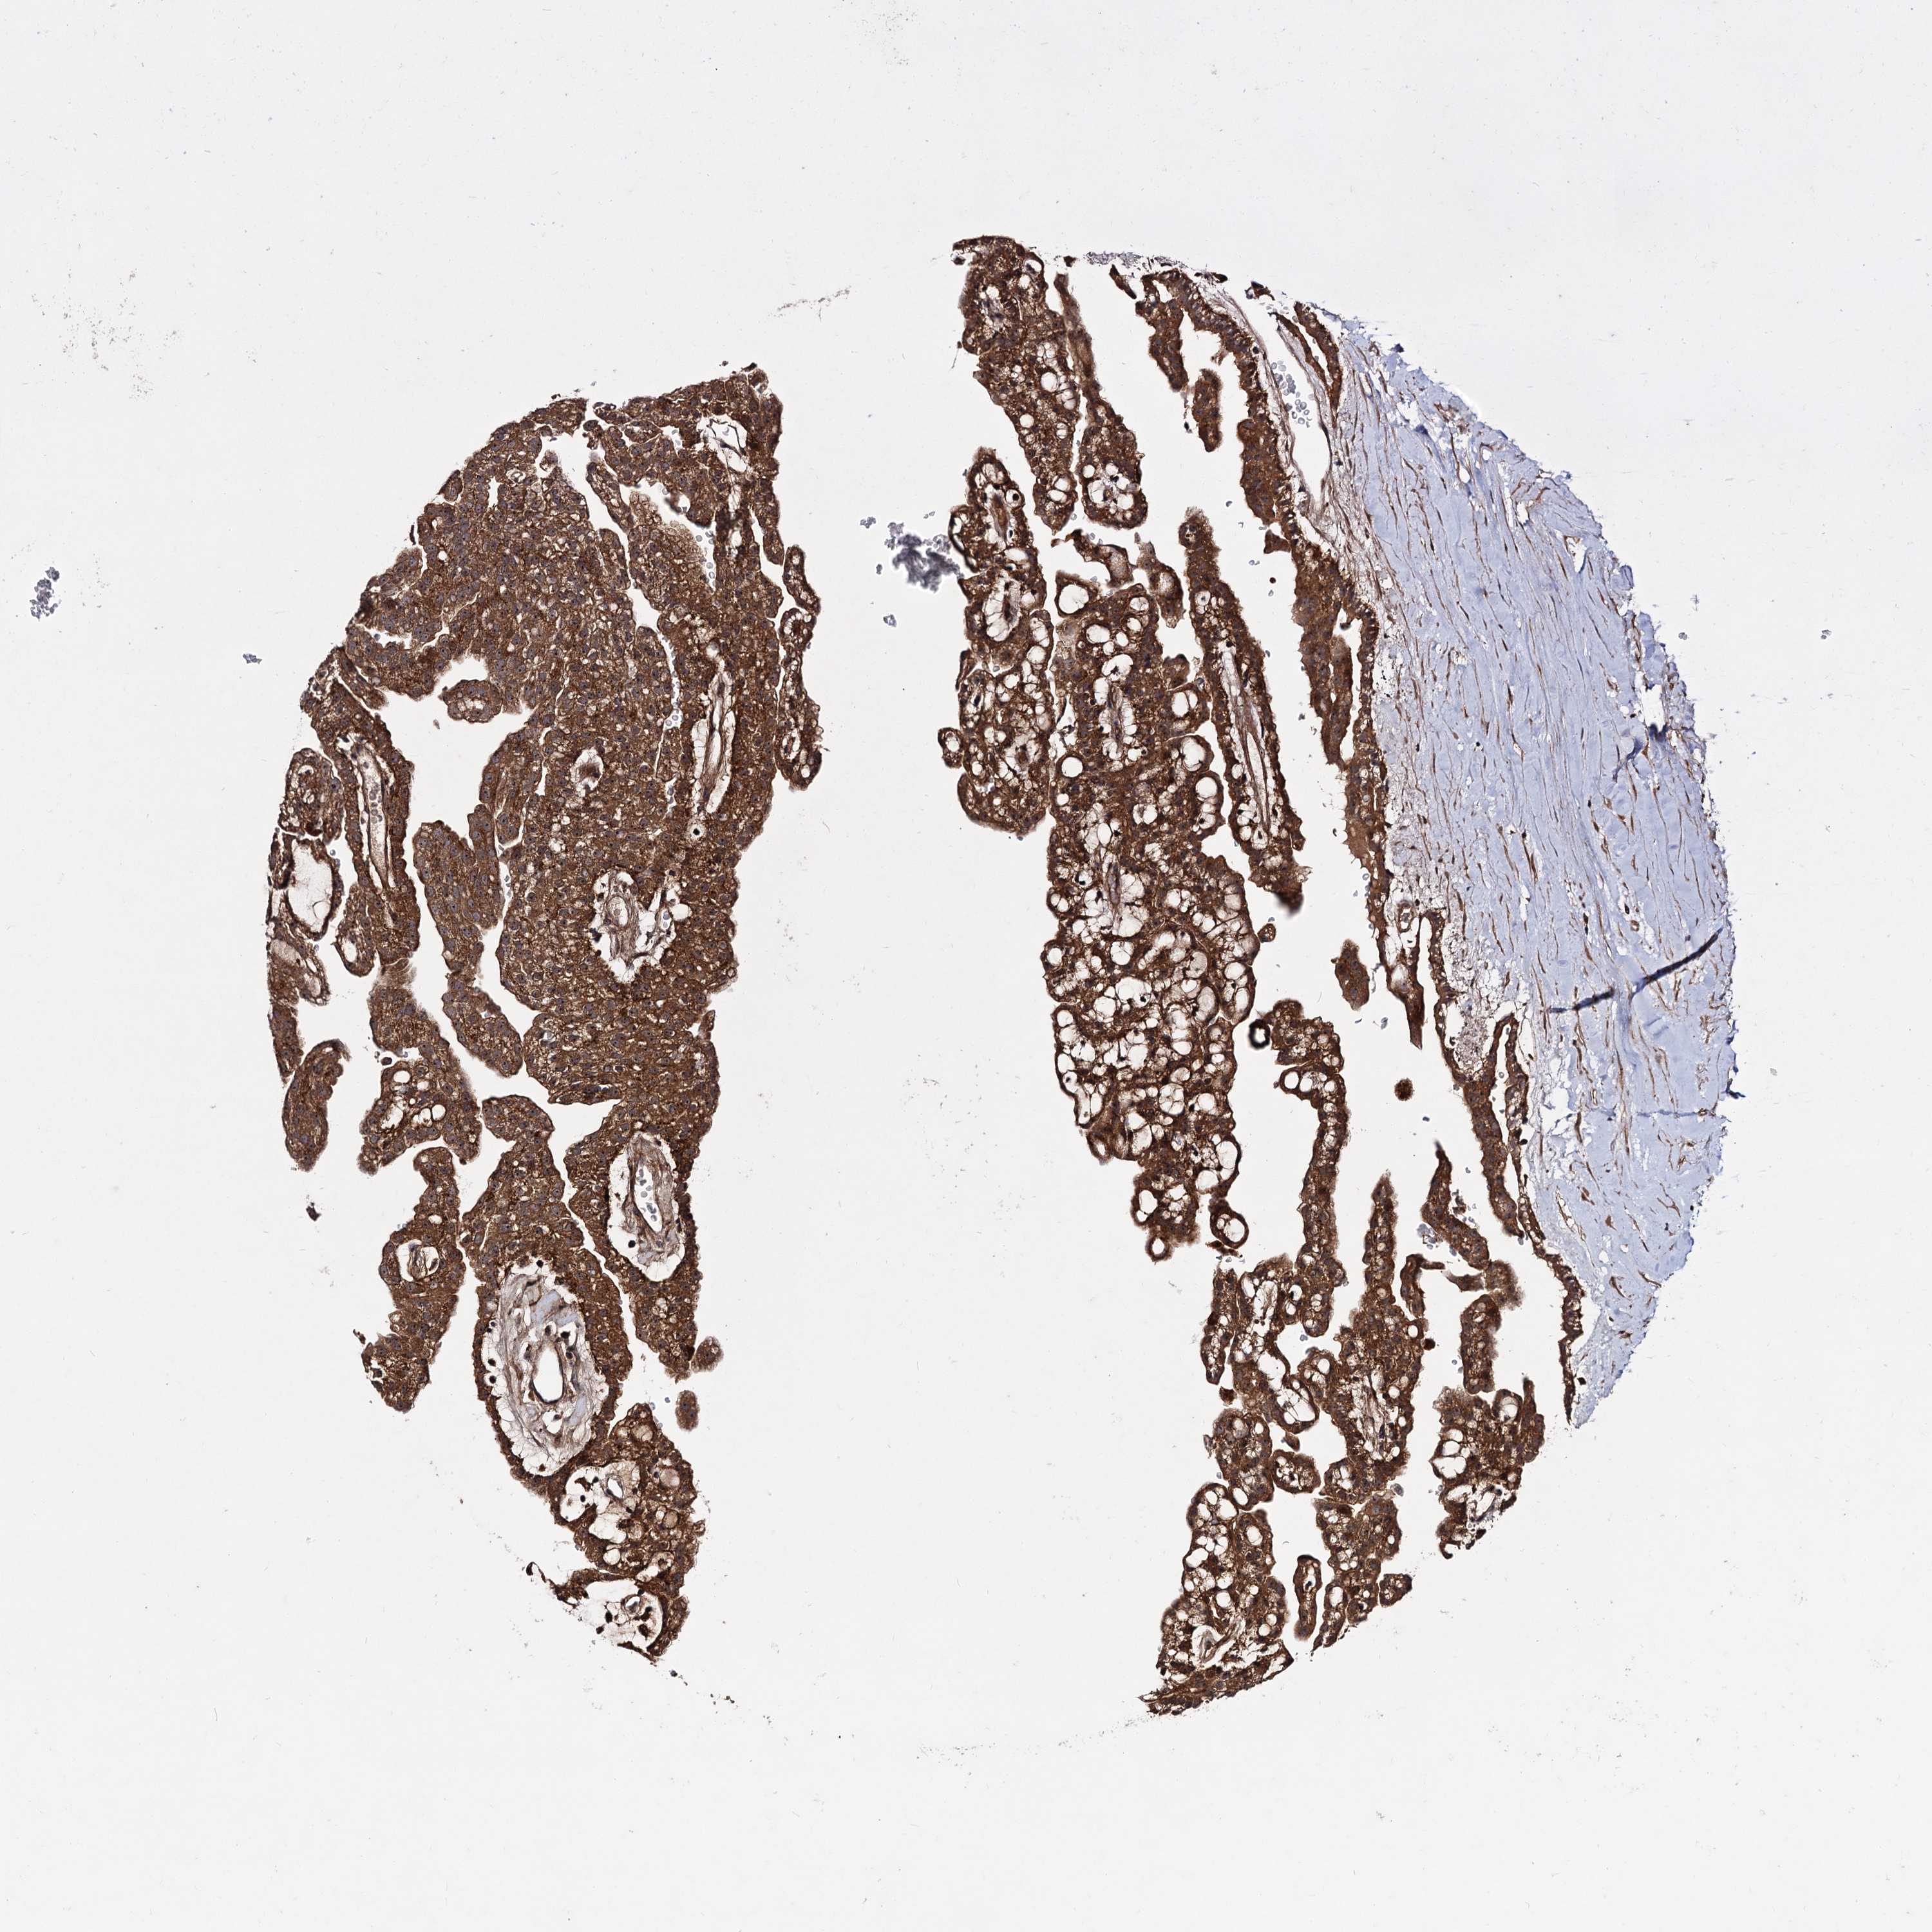

KIDNEY RENAL CLEAR CELL CARCINOMA (VALIDATION) - Interactive survival scatter ploti

The Survival Scatter plot shows the clinical status (i.e. dead or alive) for all individuals in the patient cohort, based on the same data that underlies the corresponding Kaplan-Meier plots. Patients that are alive at last time for follow-up are shown in blue and patients who have died during the study are shown in red.

The x-axis shows the expression levels (FPKM) of the investigated gene in the tumor tissue at the time of diagnosis. The y-axis shows the follow-up time after diagnosis (years). Both axes are complimented with kernel density curves demonstrating the data density over the axes. The top density plot shows the expression levels (FPKM) distribution among dead (red) and alive patients (blue). The right density plot shows the data density of the survived years of dead patients with high and low expression levels respectively, stratified using the cutoff indicated by the vertical dashed line through the Survival Scatter plot. This cutoff is automatically defined based on the FPKM cutoff that minimizes the p-score. The cutoff can be changed by dragging the vertical line or by entering a cutoff value in the square labeled "Current cut-off".

Under the Survival Scatter plot the p-score landscape (black curve; left axis) is shown together with dead median separation (red curve; right axis). Dead median separation is the difference in median mRNA expression between patients who have died with high and low expression, respectively. It is calculated as follows: median FPKM expression of dead patients with high expression - median FPKM expression of dead patients with low expression. This is intended to aid the user in visually exploring custom cutoffs and the associated p-scores and dead median separation.

Individual patient data is displayed and can be filtered by clicking on one or more of the category buttons on the top of the page. Categories describing expression level and patient information include: high, low, alive, dead, female, male and tumor stages. The scale of the x-axis can be toggled between linear and log-scale by clicking on the "x log" button. Mouse-over function shows TCGA ID, patient information and mRNA expression (FPKM) for each patient.

& Survival analysisi

Kaplan-Meier plots summarize results from analysis of correlation between mRNA expression level and patient survival. Patients were divided based on level of expression into one of the two groups "low" (under cut off) or "high" (over cut off). X-axis shows time for survival (years) and y-axis shows the probability of survival, where 1.0 corresponds to 100 percent.

KXD1 is not prognostic in Kidney Renal Clear Cell Carcinoma (validation)

Best expression cut offi

Based on the FPKM value of each gene, patients were classified into two groups and association between prognosis (survival) and gene expression (FPKM) was examined. The best expression cut-off refers the FPKM value that yields maximal difference with regard to survival between the two groups at the lowest log-rank P-value. Best expression cut-off was selected based on survival analysis .

When clicking on this number, the vertical dashed line indicating cut-off, the interactive survival plot, and the Kaplan-Meier curve will be adjusted to show results based on the best expression cut-off.

: 106.81

Median expressioni

Median expression refers to the median FPKM value calculated based on the gene expression (FPKM) data from all patients in this dataset. When clicking on this number, the vertical dashed line indicating cut-off, the interactive survival plot, and the Kaplan-Meier curve will be adjusted to show results based on the median expression.

: N/A

Median follow up timei

Median follow up time refers to the median time (years) after diagnosis with this type of cancer, based on clinical data from all patients in this dataset.

P scorei

Log-rank P value for Kaplan-Meier plot showing results from analysis of correlation between mRNA expression level and patient survival.

N/A

5-year survival highi

5-year survival for patients with higher expression than the expression cutoff.

For melanoma and glioma, 3-year survival is shown.

5-year survival lowi

5-year survival for patients with lower expression than the expression cutoff.

TCGA RNA samplesi

RNA-seq data is reported as average FPKM (number Fragments Per Kilobase of exon per Million reads), generated by the The Cancer Genome Atlas (TCGA) .

Normal distribution across the dataset is visualized with box plots, shown as median and 25th and 75th percentiles. Points are displayed as outliers if they are above or below 1.5 times the interquartile range. FPKM values of the individual samples are presented next to the box plot.

Average pTPM 95.7

Number of samples 100